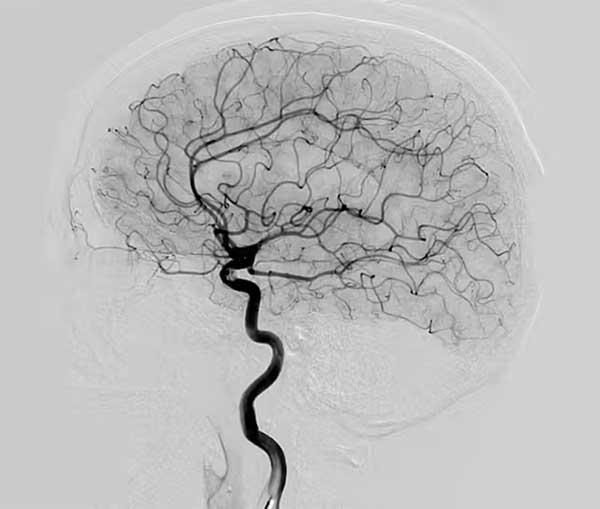

ANGIOGRAPHY

Angiography also referred to as arteriography or coronary angiogram is a medical imaging technique, a kind of X-ray used to check blood vessels, arteries, veins and heart chambers.

In angiography a special dye is needed and is injected into your blood first. This dye highlights your blood vessels, and other details allowing the doctor to see any problems. The X-ray images created during angiography are called angiograms. An angiogram can show if your coronary arteries are narrowed, where they are narrowed, and by how much. If necessary, your doctor can open blocked or narrowed heart arteries through angioplasty procedure during your coronary angiogram.